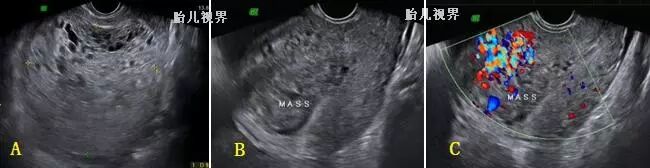

CTN即恶性的侵蚀性葡萄胎、绒毛膜癌、胎盘部位滋养细胞肿瘤(PSTT)和上皮样滋养细胞肿瘤(ETT)的总称,它们有个共同的生物特点,均由于病变已侵犯子宫肌层血管,造成血管的构筑异常;超声表现亦相似,即于宫内出现局灶型或弥漫性病灶,病灶可以为高回声、低回声、无回声或混合回声,弥漫型者子宫呈千疮百孔”状。彩色多普勒示病灶血流丰富,甚至呈五彩缤纷血流信号,且为高速低阻频谱并能见到动静脉瘘频谱(见)。需要指出的是,有种罕见情况,即双胎之一葡萄胎,合并一正常胎儿,需要与部分性葡萄胎鉴别,前者葡萄胎与正常胎儿分界清楚,存活胎儿常发育正常;而后者则于胎盘内散在囊性病灶,胎儿常发育不良。

图七、一例早孕人流后发展的妊娠滋养细胞肿瘤声像,宫底浸润,血流丰富伴宫旁侵犯(经阴道超声)

图八、一例完全性葡萄胎(左图)清宫后发展的妊娠滋养细胞肿瘤声像,前壁浸润,伴血流丰富(经阴道超声)

图九一例足月分娩后发展的妊娠滋养细胞肿瘤声像,宫内高回声团块短期内迅速增大,血流丰富(经阴道超声)